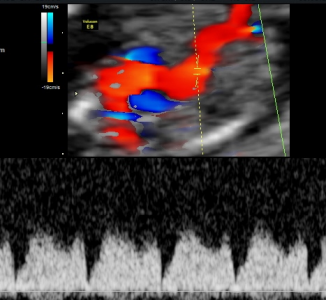

Naszym atutem jest również profesjonalny sprzęt ultrasonograficzny oraz nowoczesne wyposażenie gabinetów, którymi dysponujemy na co dzień.

Arkadiusz Krzyżanowski - na codzień pracuję w Katedrze i Klinice Położnictwa i Patologii Ciąży (Szpital SPSK1 - Staszica 16) Uniwersytetu Medycznego w Lublinie, gdzie oprócz opieki nad pacjentami w zakresie Położnictwa, Patologii Ciąży i Perinatologii zajmuję się dydaktyką studentów Wydziału Lekarskiego naszego Uniwersytetu jak i pracą badawczą. Moje najważniejsze osiągnięcia to: Doktorat z zagadnień porodu przedwczesnego, Habilitacja z zakresu pogłebionej diagnostyki prenatalnej oraz zaawansowanych badań nad komórkami macierzystymi. Jestem autorem i współautorem ponad 180 doniesień i publikacji, w tym 86 artykułów o charakterze naukowym jak i dydaktycznym w renomowanych czasopismach - wielu o zasięgu międzynarodowym. Moje zainteresowania wynikają z mojej pasji - chęci niesienia pomocy.

Perinatologia zwana też medycyną matczyno-płodową jest dziedziną medycyny zajmującą się opieką nad dzieckiem jeszcze w okresie płodowym. Celem tej opieki jest określenie najwłaściwszego sposobu prowadzenia ciąży czy możliwości wykonania ratujących życie zabiegów chirurgicznych w przypadku wykrycia w badaniach prenatalnych wady u płodu.

Dostępność badań, nowoczesny sprzęt diagnostyczny oraz specjalistyczna wiedza umożliwiają wychwycenie pewnych wad wrodzonych. Należy podkreślić, że niestety nie zawsze i nie wszystkich. Czasami możliwe jest leczenie jeszcze przed narodzinami.